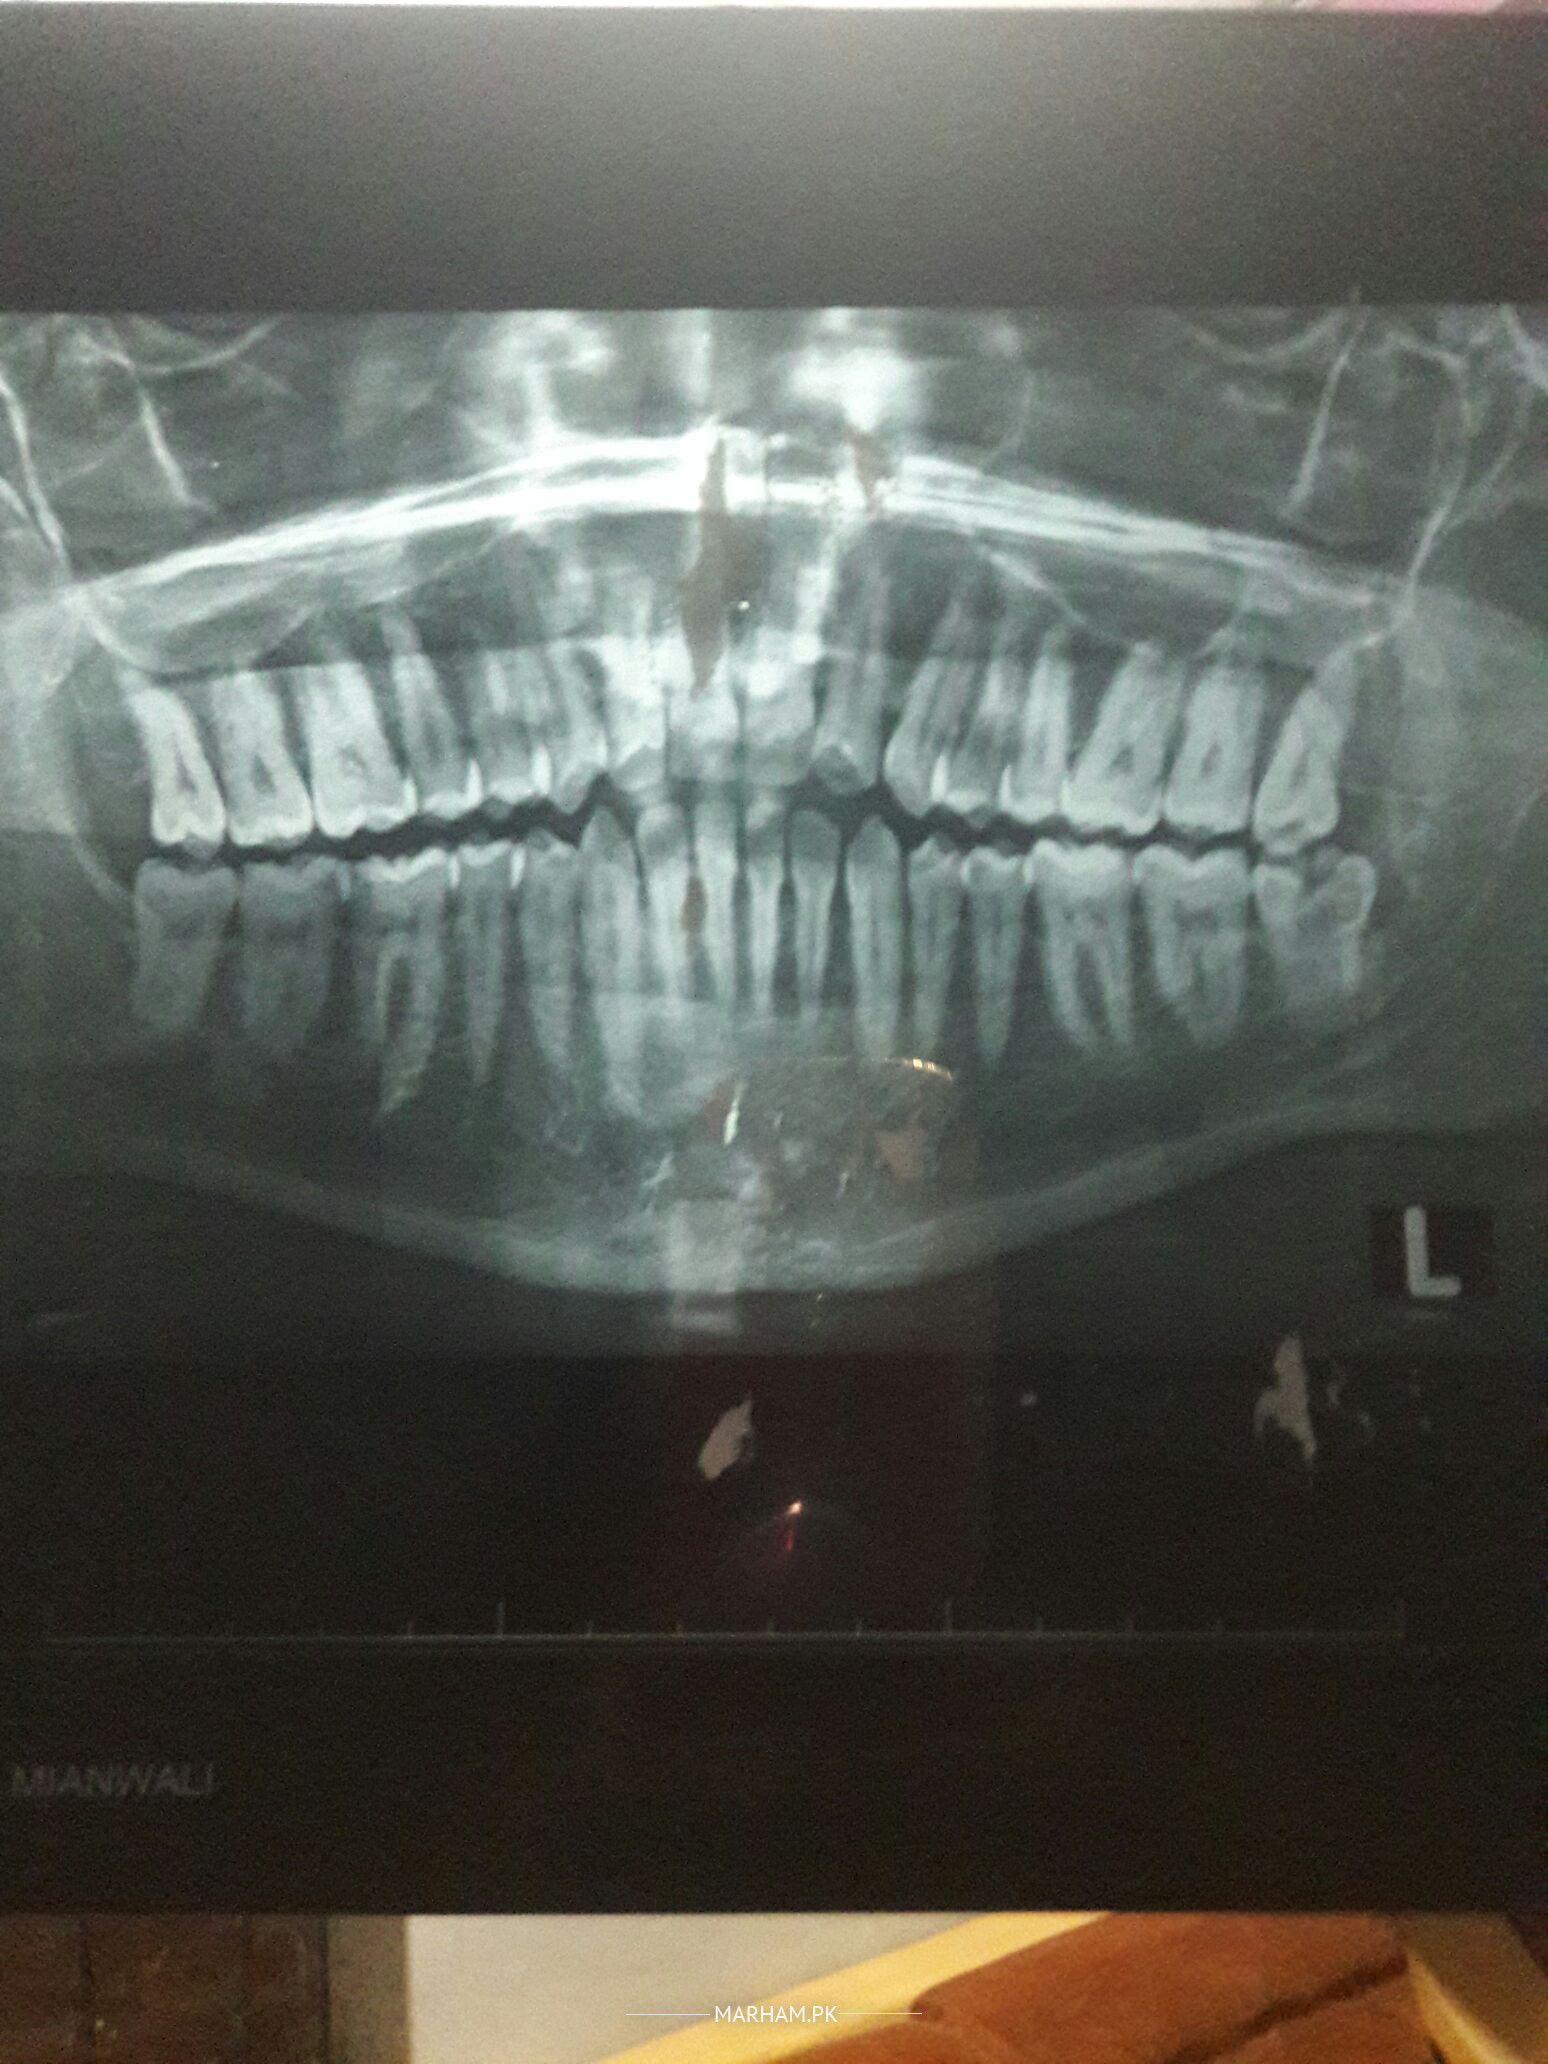

Asking For Self, Male 35, mianwali

AoA G 10 mah ho gae hain mare danton men kamzori hai danton se zor nai lagta aur left se kabhi kanpati men derd hota hai aur kabhi kaan men kindly koi ilaj bta den thanx

left side ka nechy wala dant kharab hai jis ki pain sar tk ja rahi hai uska ilaj karwain aur dant kamzor is liye hoe hain k inki safai ni hoe bone nechy chali gae hai ap danto ki safai karwa lain thk ho jae ga danton se ap aram se kha saky gy

Walekm Salam.Apke lower left wisdom tooth mey Cavity he or dant expose he.ap is dant ko extract krwayn insha ALLAH teek hojayga

Dear patient, your last tooth on the lower left side is responsible for pain . Its your wisdom tooth and they are generally extracted. Kindly book an appointment with a dentist for its removal. Thanks

visit dentist for check up. ur wisdom tooth of both upper and lower left side needs to be removed. brush twice and get teeth cleaning done also by dentist.

Walaikum Assalam on left lower wisdom there is cavity in tooth and it has to be removed. This is the reason for pain in ear. Get a deep cleaning of scaling done. In shaa Allah it will recover the bone strength of teeth